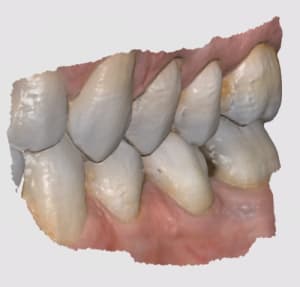

labocast_pose_33_34_35_rdggkr.jpg